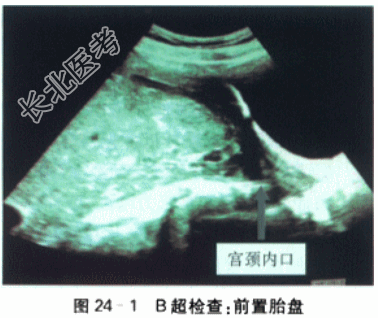

- [材料题] 产妇,25岁,因孕30⁺⁴周,无痛性阴道出血1h余来院就诊。LMP2021-12-29,EDC2022-10-6,停经30天,查尿β-HCG(+),孕2月出现轻微早孕反应(恶心、呕吐),孕5月出现胎动,胎动好,定期于外院做产前检查,2022-6-5外院超声提示单胎,胎盘后壁,胎盘下缘似部分覆盖宫颈内口。今孕妇30⁺⁴周,夜间睡眠中,突发无痛性阴道出血,量约10ml,色鲜红,内裤血迹晕染呈淡红色。遂至外院急诊,病程记录当时查体“未及宫缩,血水打湿内裤,色鲜红,阴道窥积检查:胎膜似已破,宫口未开,阴道内有中等量鲜红色血水,膝反射存在”,遂予安宝100mg,20滴/min静滴保胎,因孕妇及家属要求转上级医院,联系120后送至我院急诊,查外阴见少量血迹,阴道内未见明显血性液体流出,未及宫缩。孕妇否认外伤史,否认近期性生活史,为进一步治疗,急诊拟“G₁P₀,孕30⁺⁴周,前置胎盘,胎膜早破?”收治入院。患者近期精神可,睡眠一般,食欲佳,二便正常。无外伤手术史,无高血压心、肺、肝、肾等重大脏器疾病史。生育史0-0-0-0,平素月经规则157/30,量中,无痛经。体格检查:入院查体:营养中等,无贫血貌,水肿(-),T37.0℃,P100次/min,R20次/min,BP110mmHg/70mmHg;Ht1.60m。Wt65kg,下肢无水肿,心律齐,有力,各瓣膜听诊区未闻及杂音;双肺呼吸音清,未闻及干湿啰音;肝脾未触及,腹膨隆,神经系统(-)。产科检查:腹膨隆,胎位LOA,胎动好;未及明显宫缩,子宫张力不高,腹围96cm,宫高26cm,胎心145次/min,胎头高浮。实验室检查:A型血,RH血型阳性,抗体筛选:阴性;PT9.20s,APTT25.4s;Fg5.11g;D-二聚体0.25mg/L;纤维蛋白(原)降解产物2.70mg/L。输血前测试HCV-AB-IgG(-)0.01S/CO,TP-Ab(-)0.12S/CO,ALT15IU/LHBsAg(-)0.01IU/ml,HBsAb(+)157.42mIU/ml,HBeAg(-)0.344S/CO,HBeAb(+)0.15S/CO,HBcAb(+)9.84S/CO。血常规:CRP8mg/L,WBC8.57×10⁹/L,N85.0%,RBC3.29×10¹²/L,Hb98g/L,PCV30.2%,PLT174.00×10⁹/L。肝肾功能,尿液检查,梅毒和艾滋病实验室检查均为(-)。ECG:TⅢ倒置,aVF双相。影像学检查:B超检查:双顶径75mm,头围292mm,股骨长59mm,腹围长266mm。胎盘位置:后壁。胎盘分级:Ⅱ~Ⅲ级,胎盘主体位于子宫下段,边缘完全覆盖宫颈内口(红色箭头处)(见图24-1)。胎心测及,最大羊水池深度:60mm。脐动脉血流:S/D2.3,RI0.6,PI0.8。宫颈管长度40mm。单胎横位中央性前置胎盘EFW1660g。MRI:前置胎盘未见明显胎盘植入现象。